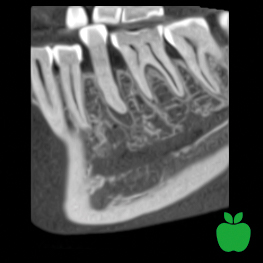

Planmeca Ultra Low Dose har visat sig vara idealiskt för ett brett spektrum av kliniska fall: från ortodonti, implantatplanering och maxillofacial kirurgi till luftvägs- och sinusstudier.